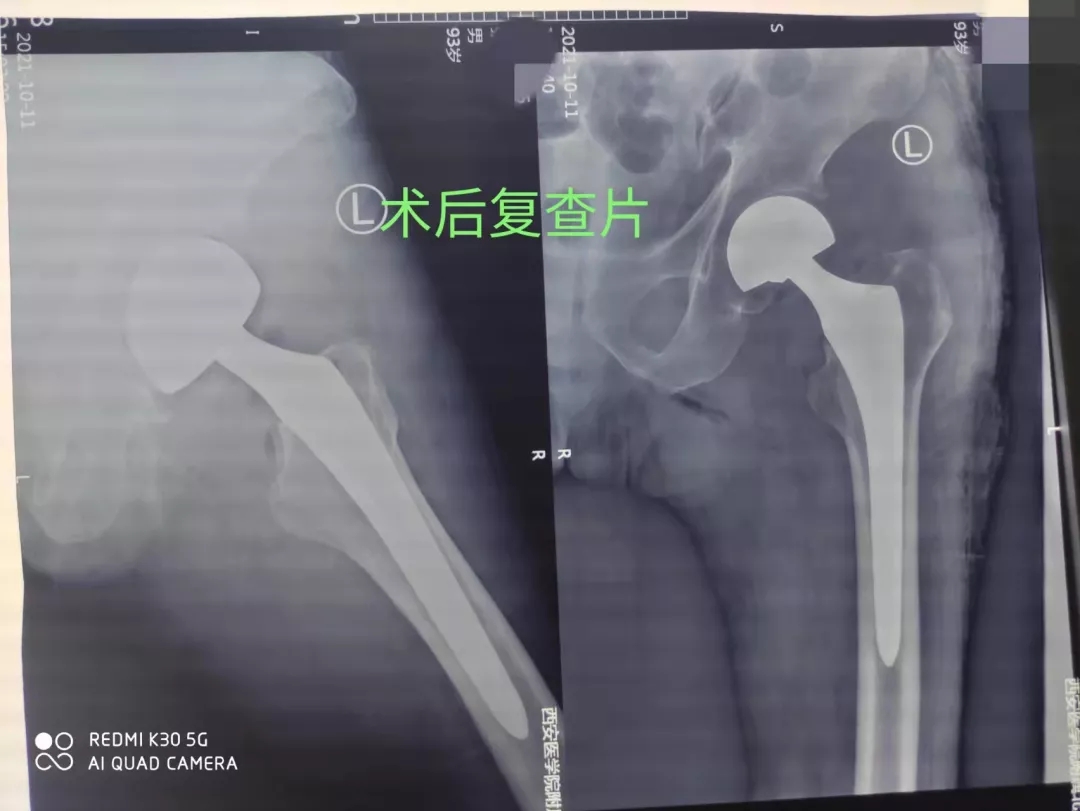

骨二科主管医生杨少洲接诊患者后,给予卧床制动,镇痛、补液、预防血栓等初步治疗。完善检查,评估患者的身体状况,经检查提示患者存在脑梗塞、脑积水、冠心病、缺血性心肌病、左前半束支传导阻滞、肾功能衰竭(代偿期)、贫血、电解质紊乱、高尿酸血症、骨质疏松等疾病。考虑患者年龄高、基础疾病多、手术风险大,告知患者家属病情及治疗方案和风险,经科室讨论后决定施行手术治疗,以便于患者早下床,减少卧床后的各种致命的并发症发生。请有关科室会诊后,骨二科为患者制定了详细周密的手术方案。凭借着丰富的临床经验和高水平创伤救治能力,在麻醉科的保驾护航下,骨二科团队用娴熟的手术技术,默契的团队配合,半小时内顺利完成左侧人工股骨头置换手术。术后24小时患者下床锻炼,1周后办理出院。

aty爱体育·(中国)平台官方网站骨二科李梁主任指出:老人髋关节周围骨折由于创伤重,并发症多,死亡率高,常常被称为“人生最后一次骨折”,老年人要特别注意,做好防滑措施。一旦不慎发生骨折,条件允许应尽快手术治疗,以便让老人在床上自如活动或下地,提高生存率和生活质量。社会逐渐步入老龄化时代,高龄患者渐增多,往往合并多基础疾病,因此该类患者治疗相对复杂,难度大,风险高,预后差。作为医务人员,有责任为患者提供有利的、相对安全的治疗措施。